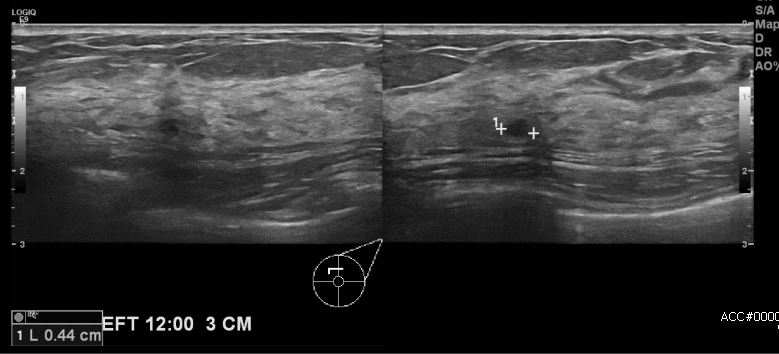

상기환자 건강검진상 이상 소견으로 내원하신 50대 여성 분으로 본원 초음파 시행 후

좌측 12시 방향에 3cm 떨어진 거리의 혹 조직검사 시행하여 좌측 유관암 진단 되었습니다.